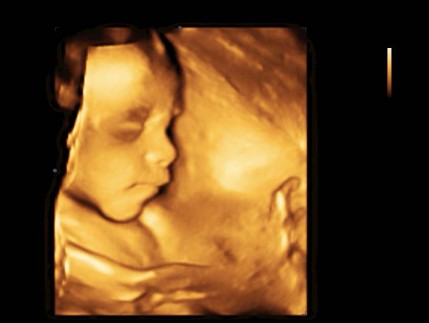

แม่ๆบ้านไหน ซาวด์ 4D กันบ้างคะ เห็นชัดกันมั้ยเอ่ย บ้านนี้ลูกสาวให้ความร่วมมือโชว์หน้าตอน 22 weeks ค่ะ???